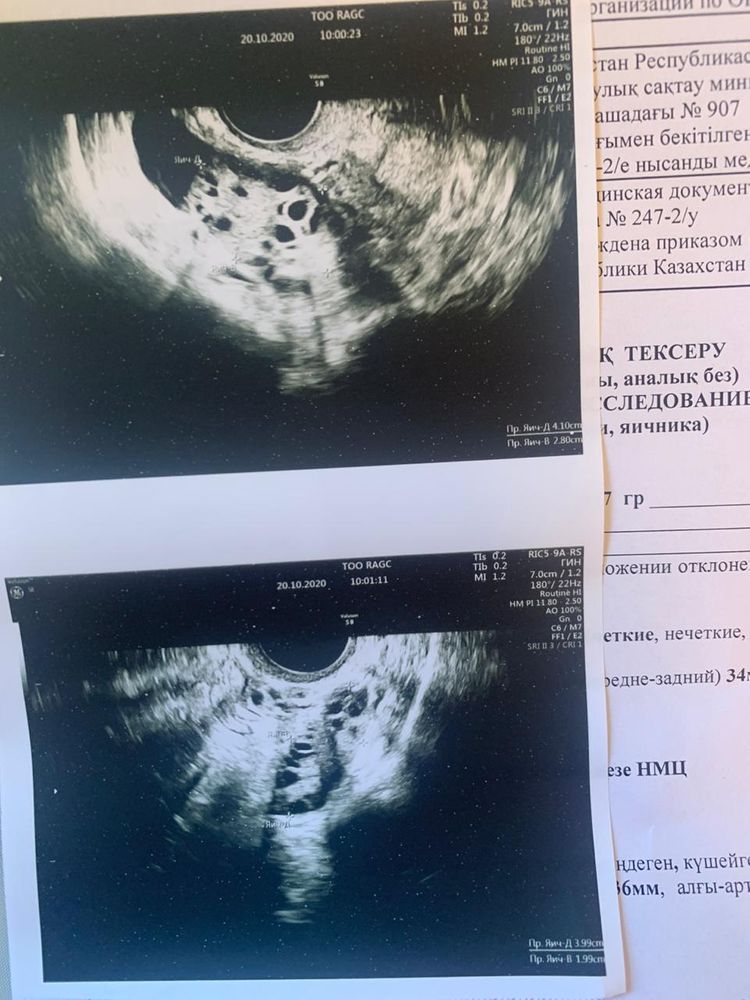

спкя первый цикл после лапары, своего цикла нет , сказали после операции пойдут 30-35 дней их нет, на узи пошла сказали скоро пойдут эндометрий две недели Наз 11 мм, жёлтого тела нет, как без желтого ттела возможна Б.либо все таки тест тупит 😭планируем уже 2 года . Вечерний тест

Все привет , у меня поликистоз . Сделали каутерезацию яичников 9 сентября . После этого месячных до сих пор нет . Последние две недели болит и налилась грудь . Неделю назад ходила на узи сказали жёлтого тела нет , в матке тоже ничего не увидели . Эндометрий 11 сказали скоро пойдут месячные . Гин сказал в течение недели . А время уже прошло а их все нет и нет 😭Живот местами тянет , как будто хотят пойти, но не могут . Очень хотим бэбика. Раньше такого не было что при задержке большой сильно болела грудь , тест - . Что это может быть ?